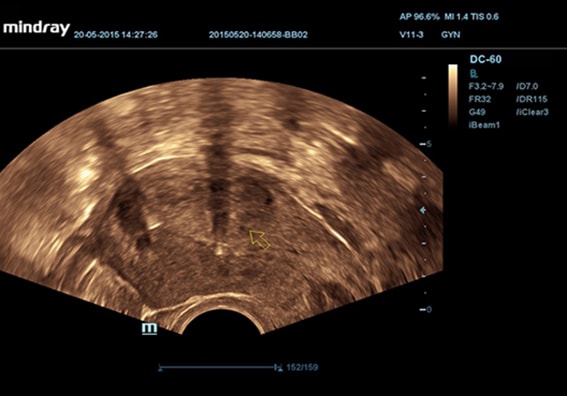

• Внутриполостной датчик Mindray V11-3

Гинекология:

Да